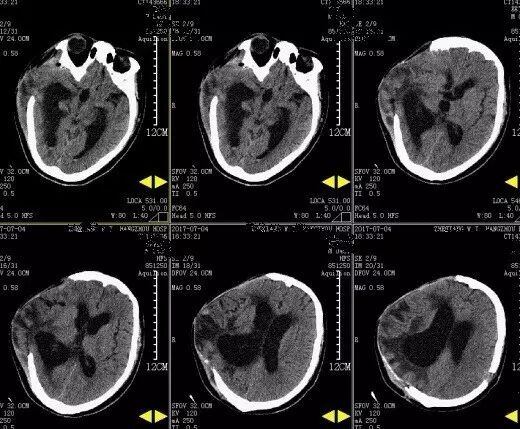

2017年5月7日上海某医院头颅CT提示:颅脑术后,双侧额颞顶部硬膜下积液积血(图4)。于2017年5月9日行双侧钻孔引流术,2017年5月12日头颅CT提示:钻孔术后改变,颅内积气(图5)。患者术后头痛症状持续加重,出现意识不清,5月15日再次复查头颅CT提示脑肿胀明显(图6),于5月17日再次行右侧硬膜下血肿清除+左侧硬膜下血肿钻孔引流术,术后患者出现脑疝,于2017年5月21日行右侧额颞顶扩大去骨瓣减压术+血肿清除术。(图7)

图7. 2017年5月22日外院头颅CT提示:右侧额颞顶部去骨瓣术后改变。

图8. 2017年7月4日本院头颅CT提示:右侧额颞顶部去骨瓣术后改变,脑室扩张。